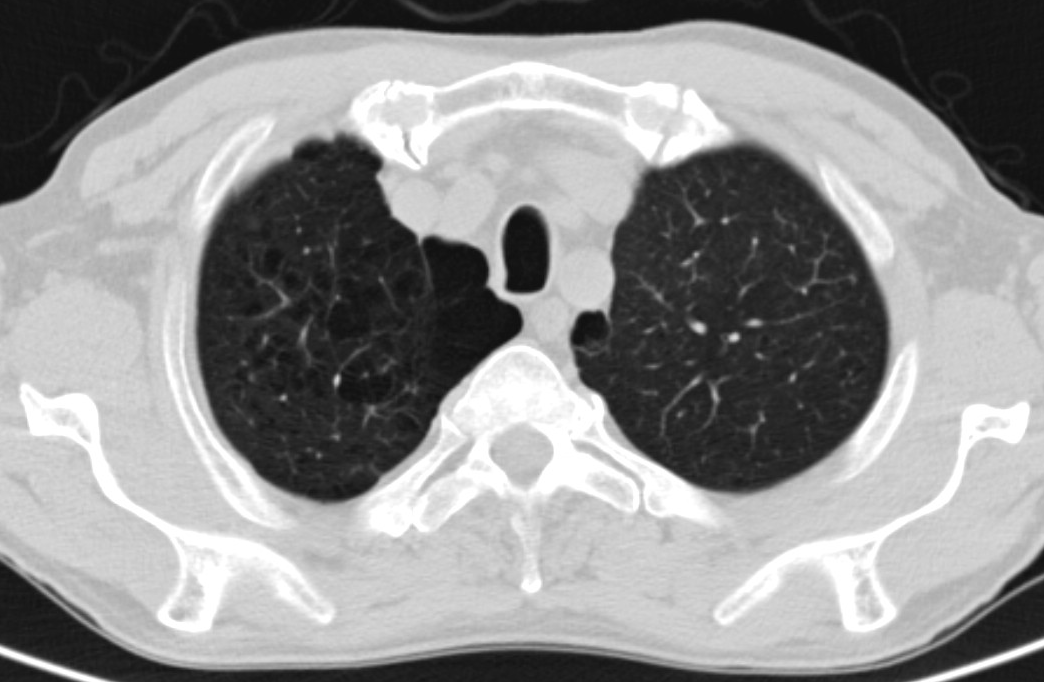

18. Tuberculosis a.) CT, b.) PA radiograph

45 year old man, pulmonary TB proven by microbiological culture.

LLL on CT: irregular, multicavitary nodular lesion: caverna.

(by the contribution of Zsuzsanna Monostori, MD, PhD)